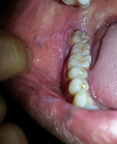

热 本院口腔扁平苔藓康复病例[真实的治疗前后对比相片] 66

李先生,一名退休公务员,患口腔扁平苔藓多年, 唇部内侧黏膜常呈白色的圆或椭圆形斑块,表面可见白色网状损害硬,常有疼痛感,都倍感痛苦,总是感觉口里很苦,而且睡眠质量也会变差,长期待折磨使得... [详情]